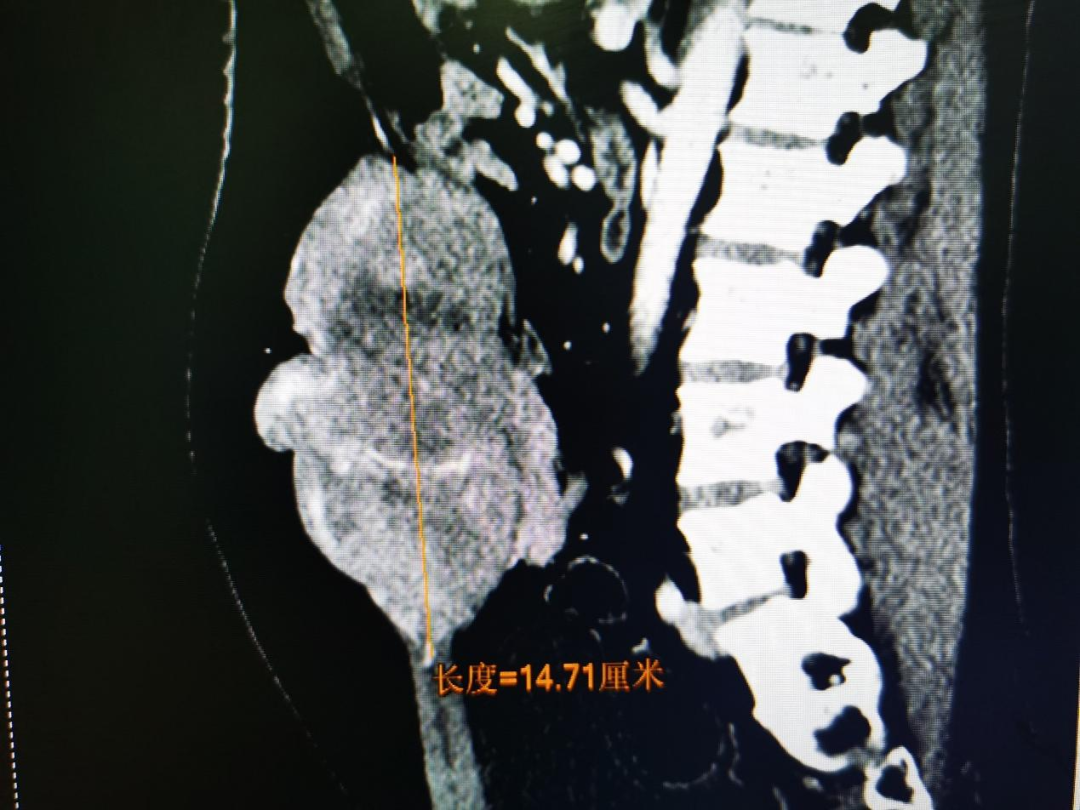

但就在半年前,腹壁肿瘤卷土重来,病情更加棘手。在当地医院束手无策的情况下,夏先生来到了中山一院烧伤与创面修复外科唐冰教授门诊。“复发的肿瘤是腹壁硬纤维瘤,也称腹壁侵袭性纤维瘤,肿瘤最大直径约15厘米,而且侵犯了腹腔的肠管,手术难度和风险都很大”唐冰说。

肿瘤最大直径约15厘米